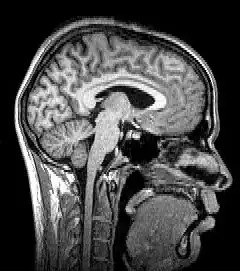

Median plane sagittal tomography of the head by magnetic resonance imaging